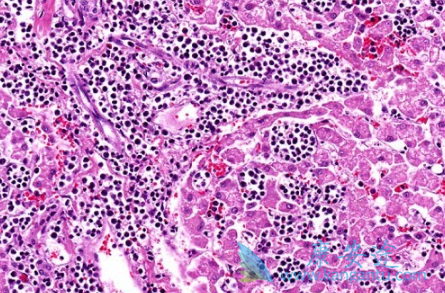

什么是血癌?血癌就是医学上的白血病,血癌只是一种俗称,在众多恶性肿瘤中,白血病是十大高发恶性肿瘤之一。那白血病传染吗?白血病是不会传染的,白血病主要是一种与血液有关的疾病,比如造血细胞出现了障碍,是造血系统的恶性肿瘤,主要与人的血液细胞有关,白血病不会传染但是却会遗传,家族里如果有一人患有白血病,那么家族的人遗传的几率为20%。

血癌常见症状有哪些?(1)淋巴结。全身广泛的淋巴结肿大,以急性淋巴细胞性白血病为多见,但急淋不如慢淋显着。浅表淋巴结在颈、颌下、腋下、腹股沟等处,深部淋巴结在纵隔及内脏附近。肿大的淋巴结一般质地软或中等硬度,表面光滑无压痛、无粘连。

(2)皮肤及黏膜病变。伴随血癌的皮肤损害表现为结节、肿块、斑丘疹等。黏膜损伤表现为鼻黏膜、呼吸道黏膜和口腔黏膜等处发生肿胀和溃疡等。(3)神经系统炎症。蛛网膜、脑膜等处可以发生白细胞浸润,表现颇似脑瘤、脑膜炎等,患者会出现颅内压增高、脑膜刺激、肢体瘫痪等症状。